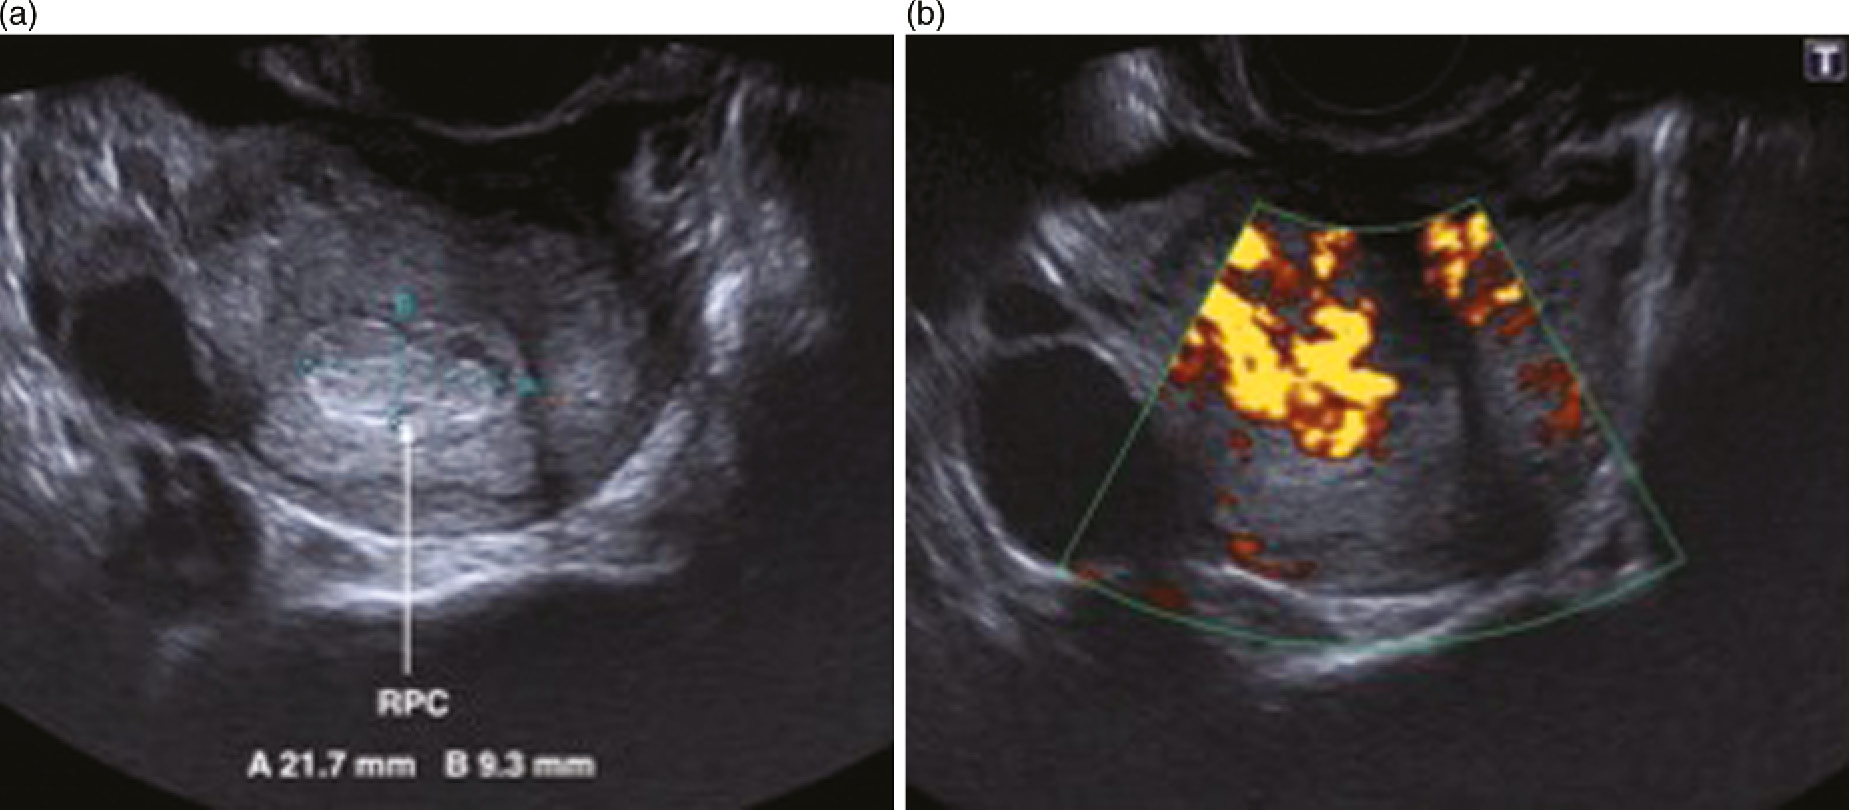

Evaluating The Transvaginal Ultrasound Diagnostic Criteria For Abnormal First Trimester Pregnancy With Follow Up Into The Third Trimester And Validation Of Results Journal Of Obstetrics And Gynaecology Canada

Abnormal Ultrasound In Early Pregnancy